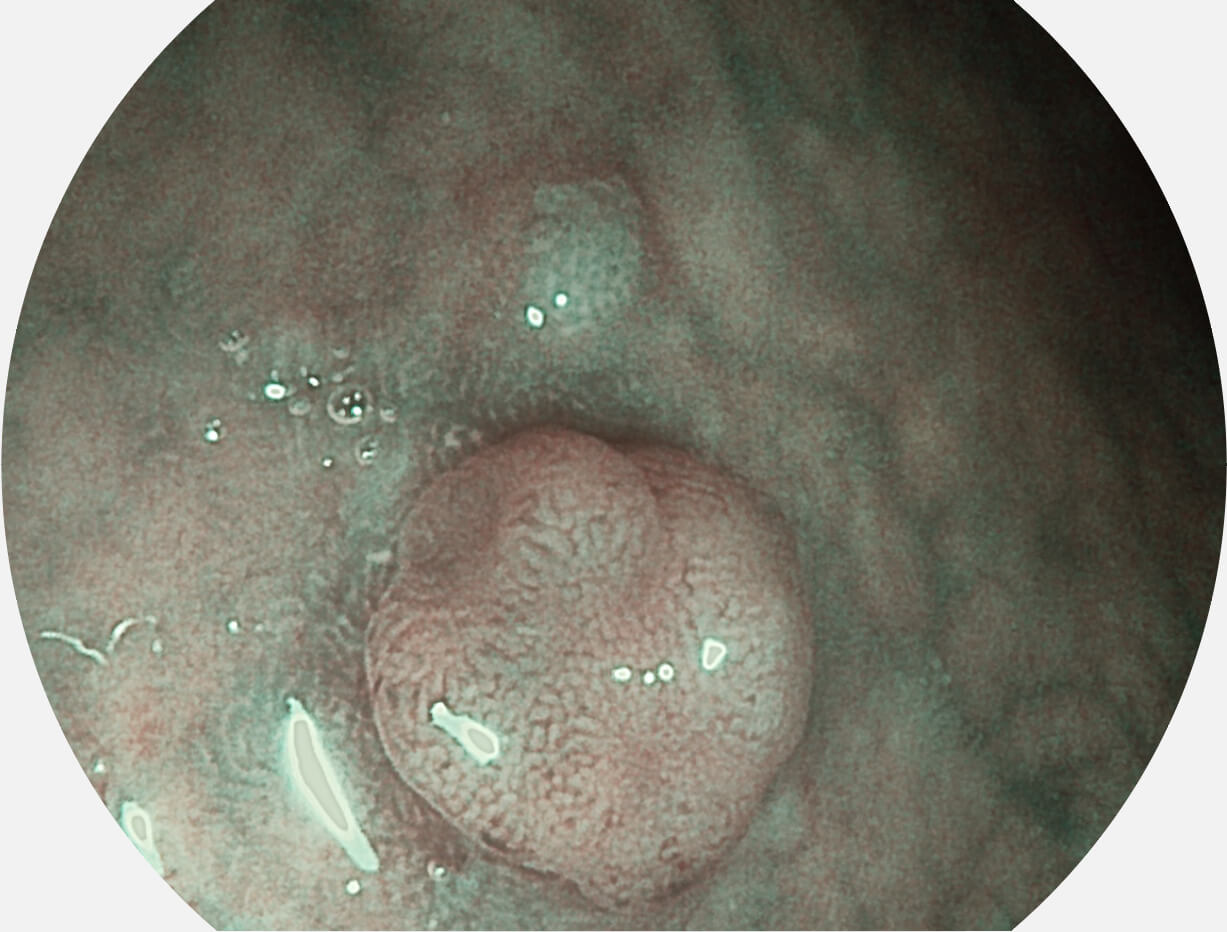

白光图像

VIST图像

Versatile Intelligent Staining Technology, VIST

强调浅层黏膜结构的同时,保证照明亮度和提升浅层微血管与中层血管颜色对比度,病变边界更清晰。